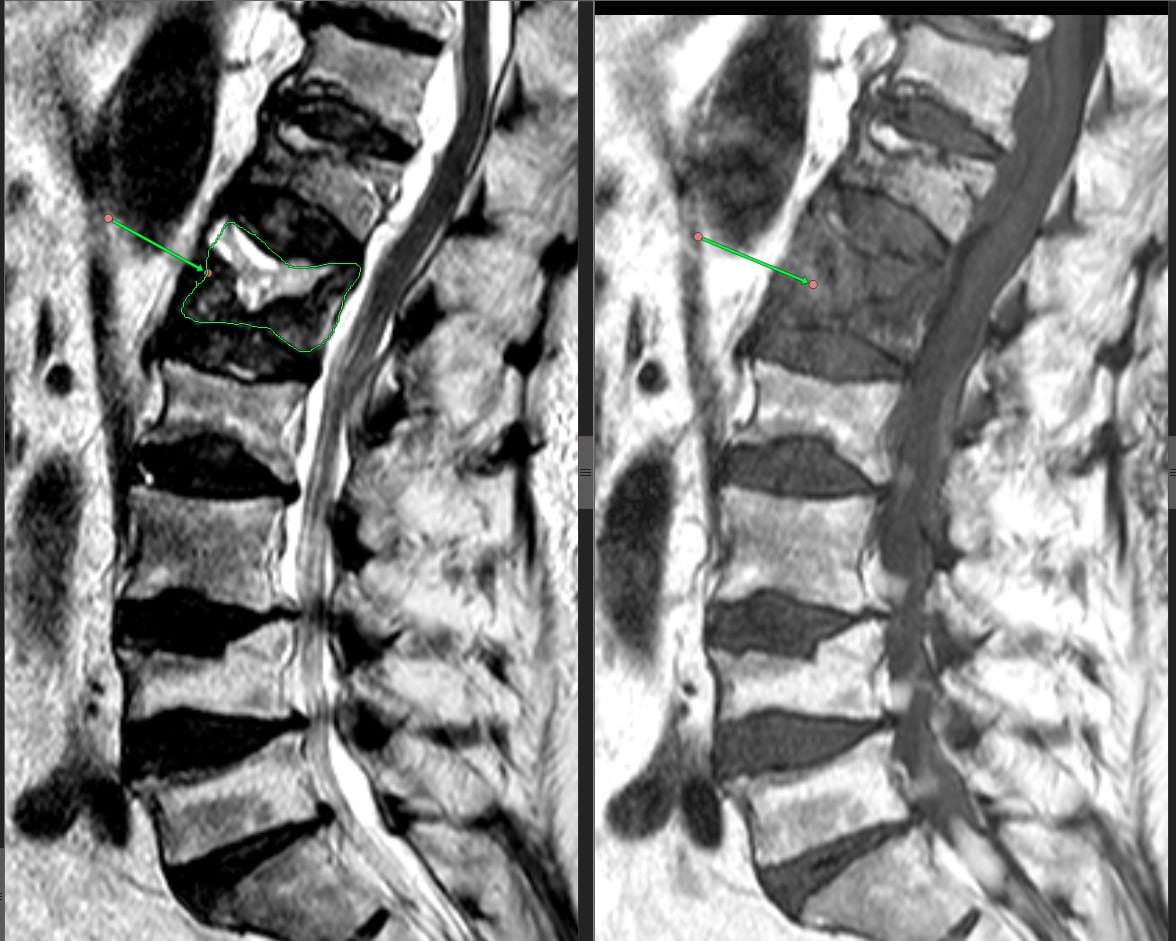

На фото - пример перелома на фоне остеопороза.

Если причина — остеопороз:

Здесь установка металлоконструкции — не панацея. Мы идем на этот шаг только при серьезных показаниях: например, если формируется выраженная деформация (патологический кифоз — «горб») с неврологическими нарушениями или нестабильность повреждённого сегмента.

Также при остеопорозе возможна вертебропластика сломанного позвонка, часто в комбинации с радиочастотной денервацией межпозвонковых суставов для снятия боли. Но! Обычно мы применяем этот метод, когда боль не уходит, несмотря на антиостеопоротическую терапию, обезболивающие и ЛФК. Эффективность таких интервенций действительно носит индивидуальный характер, и здесь могут быть споры среди коллег.